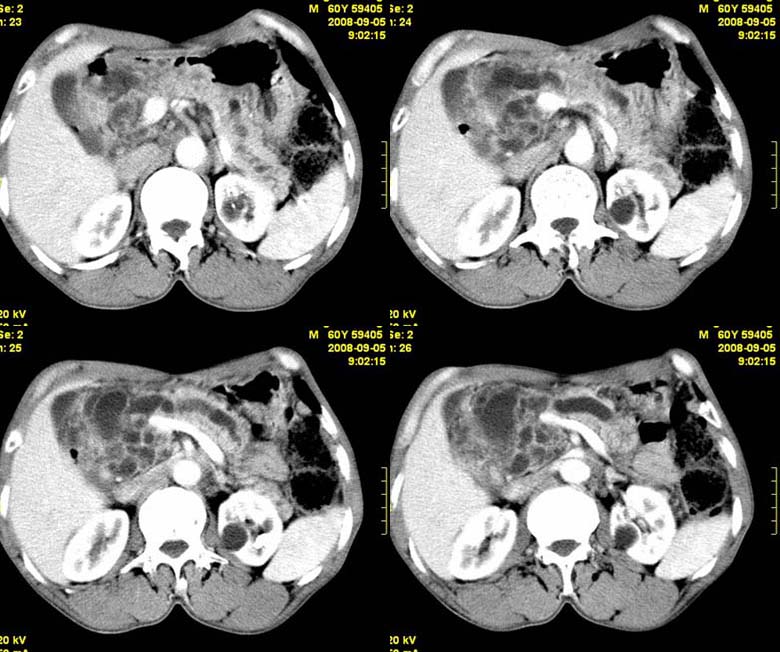

标题: CT15580:M60Y,胰腺病变,平扫+增强 [打印本页]

标题: CT15580:M60Y,胰腺病变,平扫+增强

患者,男, 60,既往有间歇腹痛病史多年,现右上腹痛,加重一月,伴右后背部疼痛,无黄疸,无发热。

考虑胰腺囊腺瘤或慢性胰腺炎

胰头区增大,胰管明显扩张,不均匀强化,且与 周围结构不清,后背疼痛,考虑为胰腺头部胰腺癌。

胰头囊腺癌

胰头囊腺癌

慢性胰腺炎

胰头囊腺癌

慢性胰腺炎并胰头癌